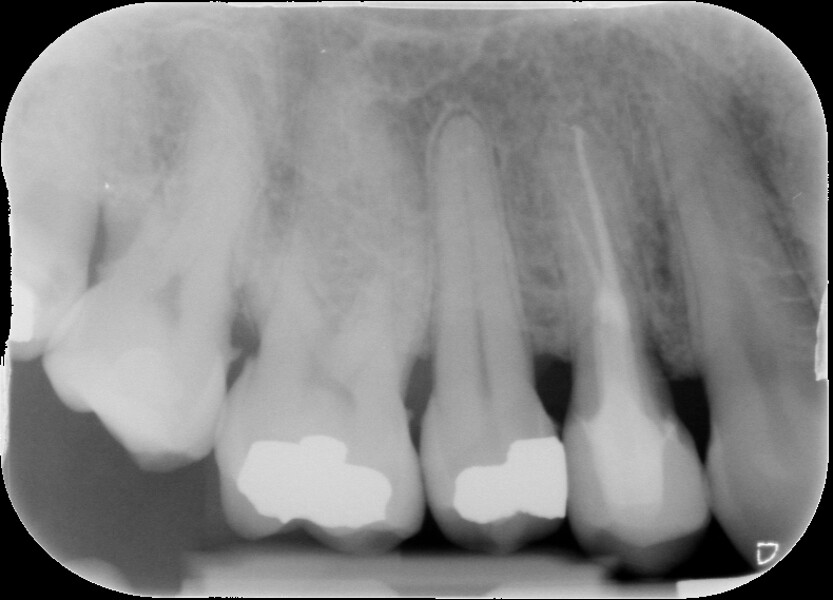

Fig. 3 : Contrôle radiographique après la finition de la prothèse.

D’un point de vue pratique, la première étape consiste à réduire les dimensions du tenon s’il occupe une grande partie de la structure coronaire, de préférence en lui donnant une forme cylindrique similaire à celle d’un tenon préfabriqué. De même, une reconstitution corono-radiculaire coulée ancrée dans plusieurs canaux doit d’abord être sectionnée jusqu’au niveau du plancher de la cavité pulpaire, afin de la traiter comme un ensemble de tenons unitaires, ce qui diminue le degré de rétention global du système. La réduction du tenon doit être effectuée avec des fraises en carbure spécialement conçues pour découper le métal, sous une irrigation abondante. Les évaluations cliniques et radiographies préliminaires sont essentielles pour planifier l’angle de coupe. La procédure doit être fréquemment vérifiée et, si nécessaire, il convient d’effectuer des contrôles radiographiques avant qu’une quantité excessive de dentine ne soit sacrifiée (Figs. 1–3).